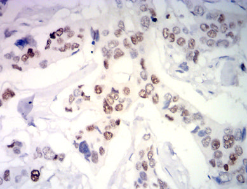

PGR Mouse Monoclonal antibody[2E4B9]

This gene encodes a member of the steroid receptor superfamily. The encoded protein mediates the physiological effects of progesterone, which plays a central role in reproductive events associated with the establishment and maintenance of pregnancy. This gene uses two distinct promotors and translation start sites in the first exon to produce several transcript variants, both protein coding and non-protein coding. Two of the isoforms (A and B) are identical except for an additional 165 amino acids found in the N-terminus of isoform B and mediate their own response genes and physiologic effects with little overlap.

Immunogen :   Purified recombinant fragment of human PGR (AA:166-411) expressed in E. Coli.

IHC    1/200-1/1000